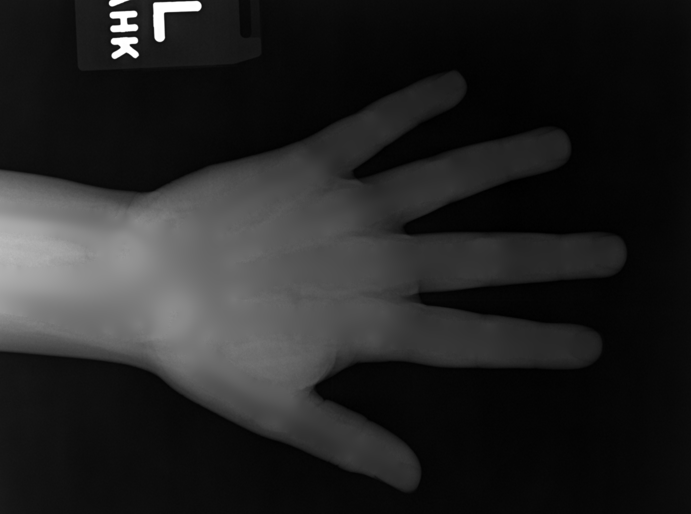

We performed three experiments for our method. First, we perform our method on several X-ray images, showing our method is not restricted by specific imaging objects. Second, we compared our method with image enhancement method and dehazing method, showing that our modification of the original dehazing indeed helps in this task. Third, we perform our method on a hand X-ray image dataset, showing its effectiveness and efficiency.

Several results from our method are shown in Fig. 7. The left column is the original input image. The right two columns are the soft tissue and bone image, respectively. It can be told that the soft tissue image is smooth as we assumed. Meanwhile, the bone image has better image contrast as desired. Moreover, our method can reach real-time performance on these X-ray images. The running time of our method on these images is reported in Table I.

In the third experiment, we applied our method on a hand X-ray image data set (RSNA), which contains more than 10,000 hand X-ray images. And the image has high resolution (usually larger than ). These images are collected from clinical applications. Therefore, we can apply our method on these practical images, showing the efficiency and effectiveness of our method on real high resolution images.

In each panel of Fig. 10, the input image (left) is decomposed into soft tissue (middle) and bone image (right) by our method. Although we only show the first ten images from the data set, the results for the rest images are similar.

The bone images have better image contrast since the parameter is theoretically guaranteed. Such enhancement can also be directly told by radiologists. Such enhancement is good for bone diagnosis in practical applications.